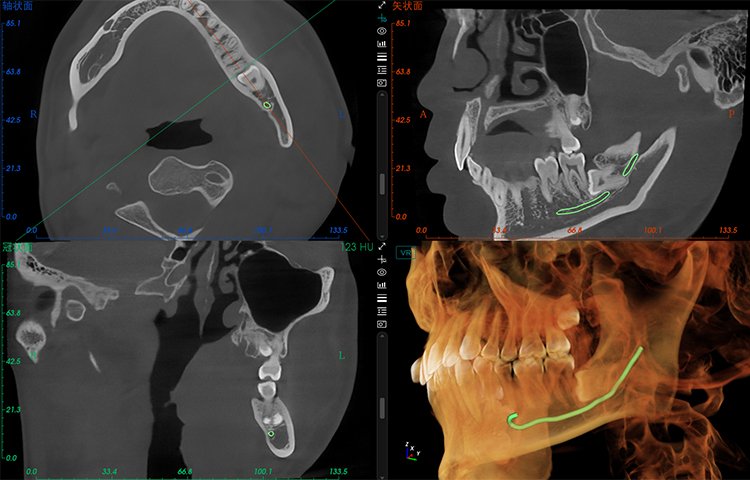

El software de diagnóstico 3D líder de Meyer y el sistema de análisis ortodóntico inteligente adoptan un diseño de UI modular, lo que hace que las funciones del software sean más cercanas a las necesidades clínicas y más fáciles de usar para los médicos, reduciendo significativamente el costo de aprendizaje.

Software de Diagnóstico 3D

MyDentViewer